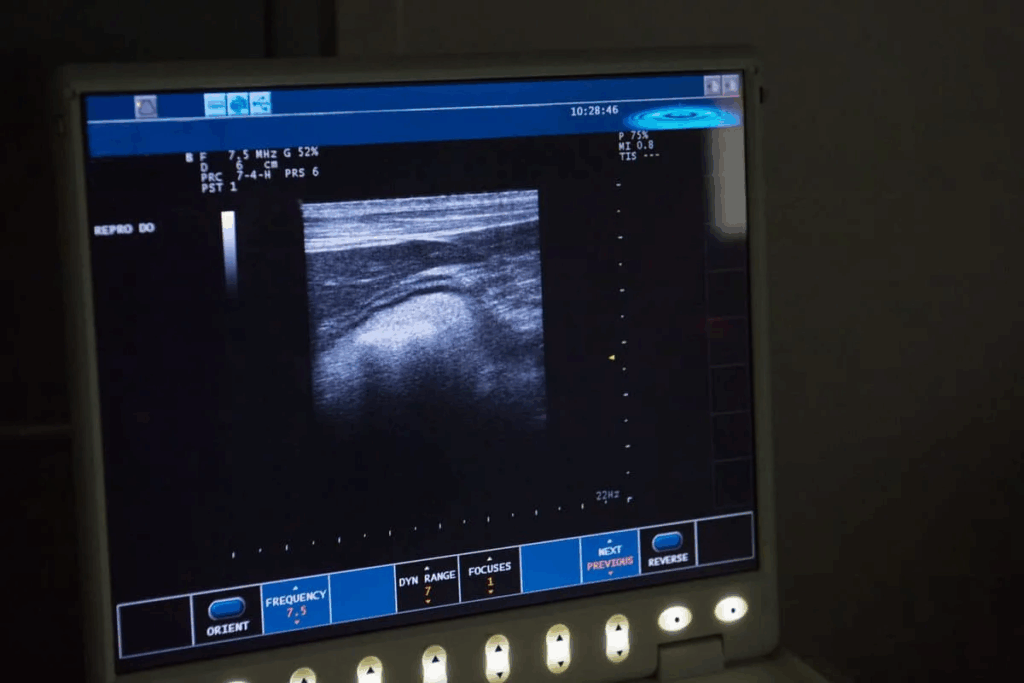

Understanding 7 Week Ultrasound Pictures

Looking at a 7-week ultrasound image can be interesting. It shows important details about your pregnancy. You might see a gestational sac, yolk sac, and fetal pole. These details help parents feel closer to their baby and understand their pregnancy better.

Interpreting Ultrasound Image Elements

Several key elements should be visible in a 7-week ultrasound. The gestational sac is one of the first signs, appearing around 4.5 to 5 weeks. By 7 weeks, it should be clear. The yolk sac feeds the embryo before the placenta forms, seen inside the gestational sac. The fetal pole is the embryo, which will grow into the fetus.

Common Visual Characteristics

At 7 weeks, the ultrasound might show a small, bean-shaped embryo. The image might not be as clear as later ones, but it’s full of valuable info. One expectant mom said, “Seeing the tiny heartbeat on the ultrasound screen was the first time I felt truly connected to my baby.” The visual characteristics of a 7-week ultrasound can vary, but they typically include a gestational sac, yolk sac, and fetal pole with a detectable heartbeat.

Remember, every pregnancy is unique. The look of ultrasound images can differ from one woman to another. The quality of the ultrasound equipment and the technician’s skill also play a role in image clarity.